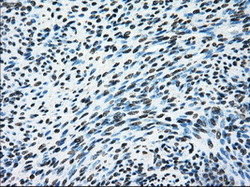

- Immunohistochemical staining of paraffin-embedded Adenocarcinoma of endometrium tissue using anti-ERCC1 mouse monoclonal antibody. (Dilution 1:50).